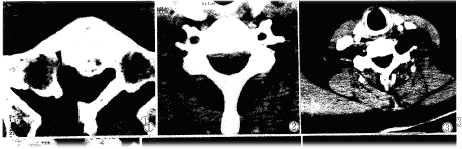

椎管肿瘤24例,以颈胸段为多(16/22),位于髓外硬膜内16例,髓外硬膜外8例。大部分椎管内神经鞘瘤肿物边界显示不清,CT表现为界线不清之软组织密度影,有的见神经根增粗,呈圆形软组织密度或表现为蛛网膜腔增宽扩大,脊髓向一侧移位(图1、2),5例见椎体骨质吸收,椎间孔扩大。

图1腰5椎管内神经鞘瘤椎间盘突出术后二年,腰5右侧神经根增粗,呈圆形软组织密度影。图2颈7椎管内神经鞘瘤,脊髓向前受压变扁,蛛网膜腔增宽扩大。图3颈动脉鞘区偏后神经鞘瘤,增强扫描强化不均匀,血管受压向前移位。图4纵隔神经鞘瘤宽基底与脊柱相连,边缘光滑,密度均匀。图5纵隔神经鞘瘤增强扫描,边缘轻度强化,中心不强化。图6臂丛神经鞘瘤,边缘光滑,密度均匀。图7腹腔恶性神经鞘瘤,肿瘤不规则,密度不均,见大片液化坏死区。图8神经鞘瘤病理见瘤细胞呈栅栏状改变(×40)